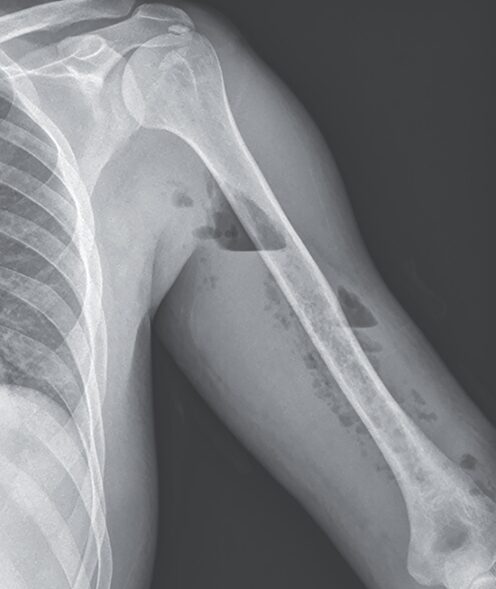

壊死性筋膜炎:レントゲンで分かる症例

37歳男性。サッカーの練習中に腕に鈍的外傷を負った後、1週間前から左上腕に痛みと腫脹が出現し救急外来を受診した。 既往としてオピオイド依存症の病歴があり、ブプレ…